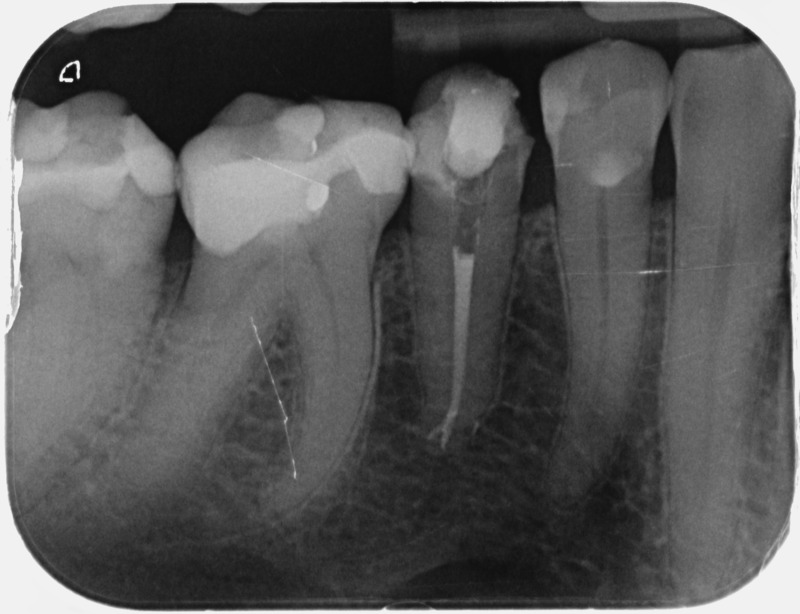

• Reprise de traitement endodontique : La manœuvre consiste à retourner à l’intérieur des racines d’une dent déjà traitée. Il arrive occasionnellement qu’une nouvelle inflammation se déclare suite à une reprise de carie ou une fracture de la dent, ou si le premier traitement endodontique est incomplet. Après s’être assuré que la dent lésée était conservable, il convient de désinfecter de nouveau le réseau canalaire parfois très complexe. La nouvelle obturation des canaux devra être protégée aussi rapidement que possible pour éviter une éventuelle contamination bactérienne.

Avant